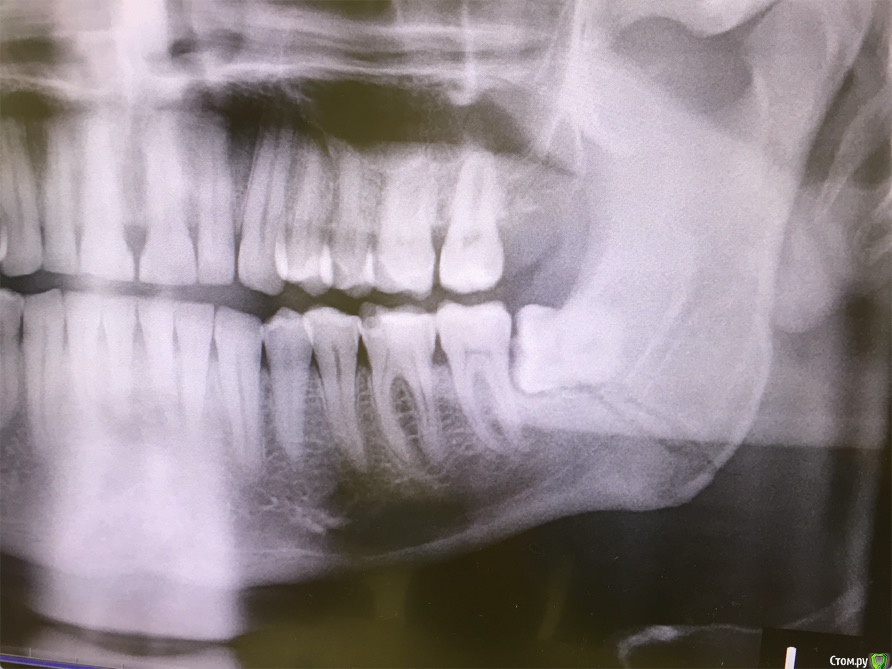

cinovka Опубликовано 10 сентября, 2015 Поделиться Опубликовано 10 сентября, 2015 Здравствуйте. Помогите советом. 15 августа получил перелом нижней челюсти с левой стороны в районе 7-8го зуба.25 числа наложили титановую пластину на место перелома и зашинировали. 3 сентября сняли шины. Разрез делали в ротовой полости и снаружи, для закрутки шурупов.Наружную рану опять вскрыли 1го сентября, т к началось нагноение. Гной выходит постоянно уже 9й день. все болит. зуб мудрости лежит в десне и очень сильно болит.Прошла неделя после снятия шин, а рот также не открылся. максимально открывается на 1-1,2 см.Я нахожусь за границей и врач мой толком ничего не обьясняет.Ответьте пожалуйста на следующие вопросы : 1) Кода пройдет нагноение? И почему оно произошло? (антибиотики, повязки и полоскания постоянные). 2) Когда откроется челюсть? 3) Когда можно будет удалить лежачий зуб мудрости? Снимки номер 1,2,3,4 сделаны до операции 17 августа.Снимки номер 5,6 сделаны сегодня 10 сентября. Заранее спасибо за ответы. Жду с нетерпением. Алексей. Ссылка на комментарий

kriokov Опубликовано 10 сентября, 2015 Поделиться Опубликовано 10 сентября, 2015 Вопрос с костным фрагментом слева,возможно он секвестрируется. чего пациента пугать. Там только два фрагмента, большой и малый, две "линии перелома"- это просто обычная картинка , редко когда ломают челюсть как по линейке, равнозначно с вестибулярной и язычной поверхности. Короче-- не секвестр 3 Ссылка на комментарий

колесников Опубликовано 10 сентября, 2015 Поделиться Опубликовано 10 сентября, 2015 Короче-- не секвестрна последнем снимке не всё так очевидно,+ гноетечение из этой области, + сроки... короче зуб не дам . 1 1 Ссылка на комментарий

ПалСаныч Опубликовано 10 сентября, 2015 Поделиться Опубликовано 10 сентября, 2015 С колесниковым не согласен категорически. Полностью поддерживаю криокова. Это не секвестр, это наложение двух линий перелома с внутренней и наружной стороны. Если б ко мне попал пациент с такой проблемой, то я предложил бы ему такую тактику: 1 пластины снять нафиг, потому чо они там не работают, ибо наложены стнарушением правил остеосинтеза, а так же потому что в ране гной; 2 во время снятия пластин через разрез задренировать рану и провести антибактериальную терапию; 3 наложить опять шины если есть подвижность отломков после снятия пластин. 4 зуб убрать вместе с пластинами. Все написанное ИМХО. 6 1 Ссылка на комментарий

cinovka Опубликовано 11 сентября, 2015 Автор Поделиться Опубликовано 11 сентября, 2015 У Вас остеомиелит челюсти.Если зуб не удалить,перелом не зарастёт никогда.Надо решать этот вопрос незамедлительно.Вы в каком городе находитесь сейчас?Есть ли возможность вернуться в Москву?Вы уверены: что у меня остеомиелит? Врач сказал, что его нет. Предоставление снимки сделаны круговым рентгеном, а не просто с левой стороны. Врач пояснил, что поэтому кажется что там две трещины. Возможно Вы в курсе, извините. Ссылка на комментарий

kriokov Опубликовано 11 сентября, 2015 Поделиться Опубликовано 11 сентября, 2015 1. По Вашим жалобам и клинике тянет на остеомиелит, точно только очно можно2. Вам сделали оптг, аппарат ходил кругом как Вы выразились. При таком снимке, да и при выполнении снимков другими методами линий перелома кажется что две, на самом деле плоскость перелома одна (ПалСаныч выше описал)3.учитывая, что гноетечение и со стороны полости рта в обл 8 и снаружи из послеоперационной раны и отек лица держится выраженный я бы члх еще раз потревожил, не решите на месте, надо возвращаться. Имхо Ссылка на комментарий